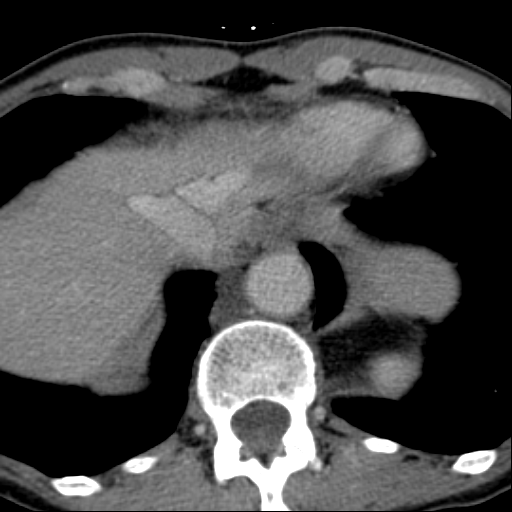

Обнаружилось небольшое образование низкой плотности, с достаточно ровными, четкими контурами парааортально справа около ножки диафрагмы на уровне тела L1 позвонка.

При нативе плотность 6HU, паренхиматозная - 18-20HU, экскреторная (15 минут) - 60-65HU.

Выкладываю по очереди срезы на одинаковых уровнях, сначала паренхиматозная, потом отсроченная фазы.